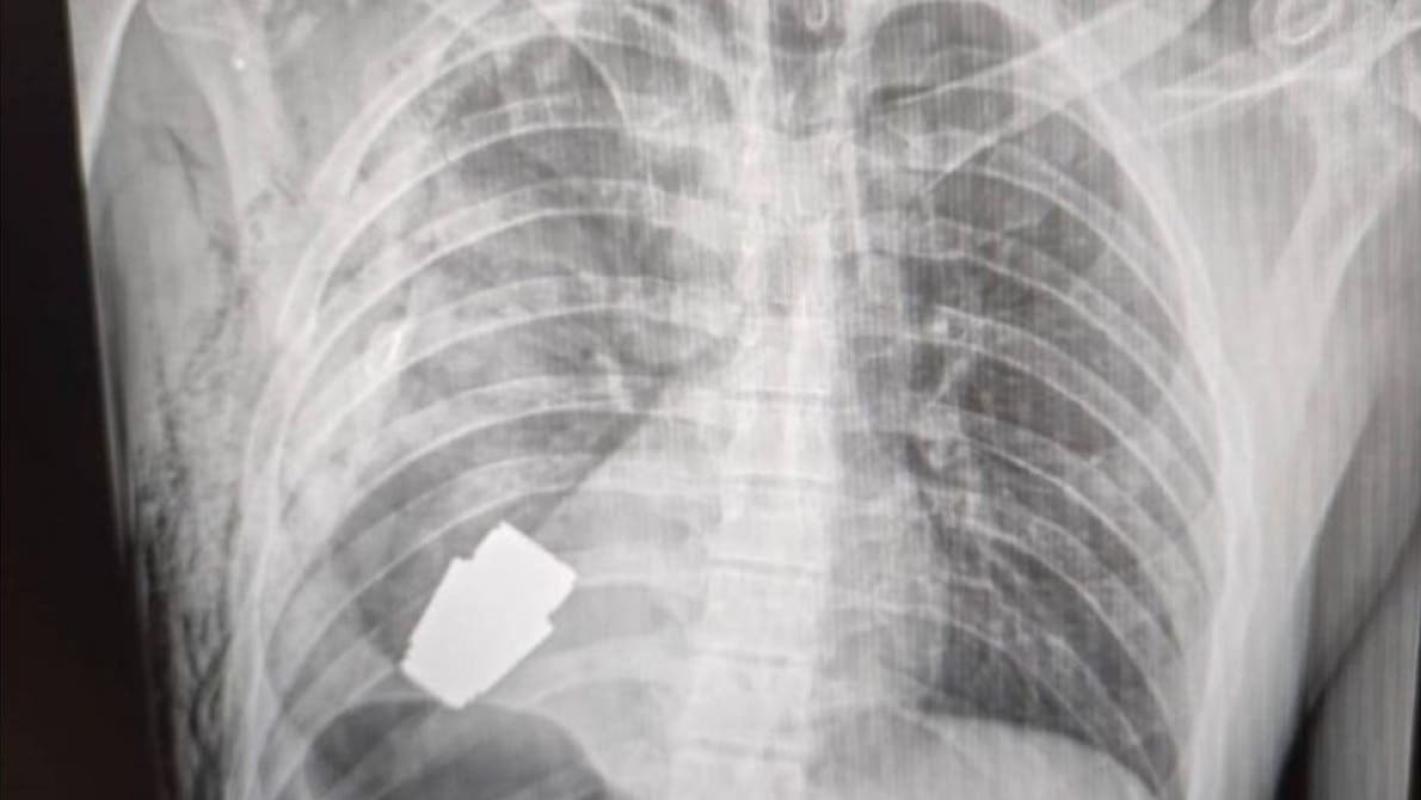

Un soldado ucraniano se sometió a una peligrosa y exitosa operación, en donde le extrajeron una granada sin estallar desde el interior de su pecho. Los cirujanos sacaron el arma explosiva justo por debajo del corazón.

"Tras tratarse de una operación con armas explosivas, se llevó a cabo sin usar electrocoagulación, es decir, sin uno de los métodos fundamentales para controlar el sangrado durante una cirugía. La granada podría detonar en cualquier momento”, dijo Hanna Maliar, viceministra de defensa de Ucrania.